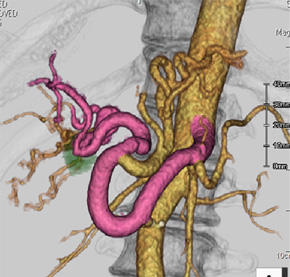

傍腎動脈型腹部大動脈瘤に対する枝付きステントグラフト